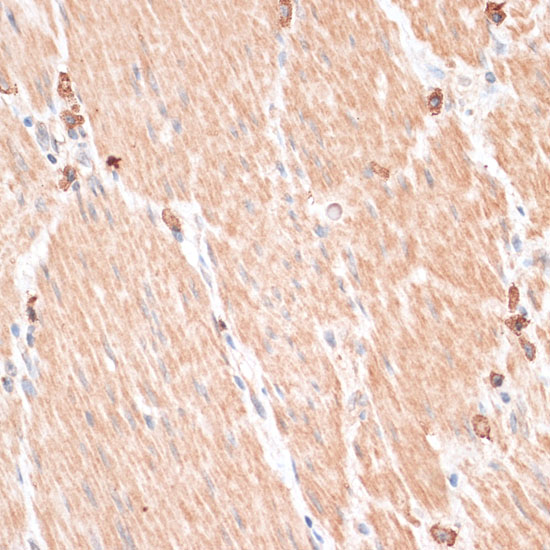

Immunohistochemistry of paraffin-embedded rat heart using ABCB7 at dilution of 1:100 (40x lens).

Immunohistochemistry of paraffin-embedded mouse brain using ABCB7 at dilution of 1:100 (40x lens).